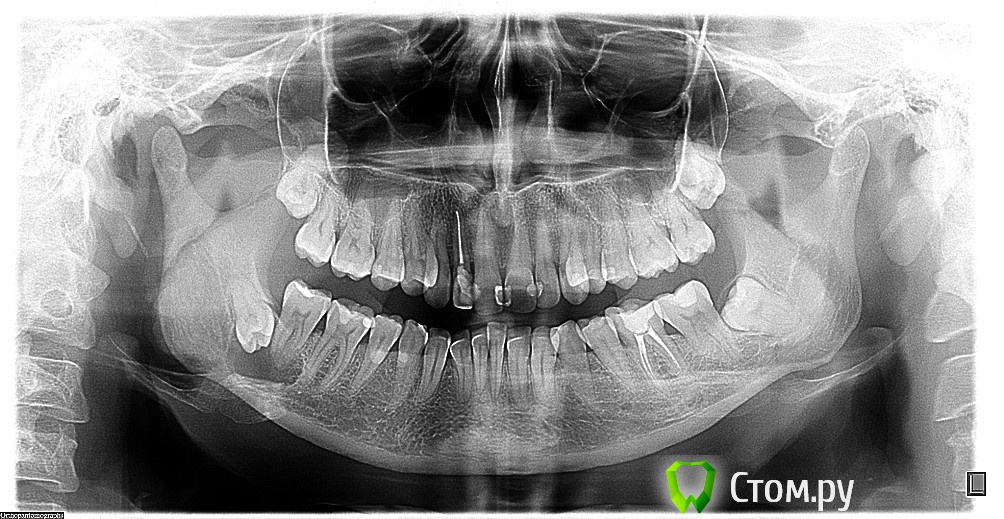

Ольга Ф Опубликовано 1 июля, 2014 Поделиться Опубликовано 1 июля, 2014 Здравствуйте!В понедельник обратила внимание на то, что при прикосновении к щеке снизу справа, незначительные болезненные ощущения, заложенность уха, небольшое уплотнение в щеке внизу ближе к челюсти. Вечером немного опухла щека.Во вторник в первой половине дня внешне щека лучше, болей почти нет. Сделала рентгеновский снимок (результат прилагаю).Записалась на прием к хирургу (в частную стоматологию) в четверг вечером.Однако к ночи (вторник) стал болеть зуб при надавливании.Мой возраст – 37 лет.Подскажите, пожалуйста:1) Возможно ли лечение в амбулаторных условиях или в моем случае необходима госпитализация и лечение в стационаре?2) Если боли не будут усиливаться, могу ли я ждать приема врача еще 2 дня (доктора, к которому записалась, мне очень рекомендовали)?3) Нужно ли делать КТ или рентгеновский снимок достаточно информативен?4) Зубы по соседству с зубом мудрости можно ли сохранить?Буду очень благодарна за любую информацию по моей ситуации. Ссылка на комментарий

Жандос Муратович Опубликовано 2 июля, 2014 Поделиться Опубликовано 2 июля, 2014 Здравствуйте!В понедельник обратила внимание на то, что при прикосновении к щеке снизу справа, незначительные болезненные ощущения, заложенность уха, небольшое уплотнение в щеке внизу ближе к челюсти. Вечером немного опухла щека.Во вторник в первой половине дня внешне щека лучше, болей почти нет. Сделала рентгеновский снимок (результат прилагаю).Записалась на прием к хирургу (в частную стоматологию) в четверг вечером.Однако к ночи (вторник) стал болеть зуб при надавливании.Мой возраст – 37 лет.Подскажите, пожалуйста:1) Возможно ли лечение в амбулаторных условиях или в моем случае необходима госпитализация и лечение в стационаре?2) Если боли не будут усиливаться, могу ли я ждать приема врача еще 2 дня (доктора, к которому записалась, мне очень рекомендовали)?3) Нужно ли делать КТ или рентгеновский снимок достаточно информативен?4) Зубы по соседству с зубом мудрости можно ли сохранить?Буду очень благодарна за любую информацию по моей ситуации.1.Стационар2.нет3.нужно4.47 скорее всего нет. 46-ЭОД(проверить жив или нет)-затем решать с ним Ссылка на комментарий

dr-krasnov Опубликовано 2 июля, 2014 Поделиться Опубликовано 2 июля, 2014 1. Можно (если есть квалифицир. хирурги)3. Конусно-лучевая томография показана. Для уточнения взаимного расположения зубов и фолликулярной кисты.4. Поддержу коллегу. 1. можно и амбулаторно2. лучше, чтобы врач сейчас посмотрел и тогда определитесь 3. кт желательно4. 46- оставлять надо, 47- шансы тоже есть Ссылка на комментарий